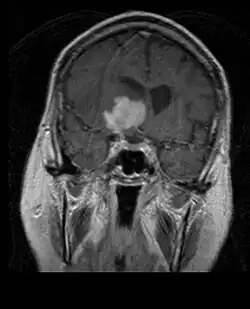

A tomografia computadorizada (TC) e a ressonância magnética (RM) podem detectar efetivamente uma neoplasia no cérebro. A RM é mais sensível que a TC para identificar lesões, mas contraindicações para pacientes com marcapasso cardíaco, próteses incompatíveis, clipes metálicos e outros. A TC continua sendo o método de escolha para detectar calcificações dentro de lesões ou erosões ósseas da calota craniana ou da base. A utilização de agentes de contraste, que são iodados no caso da TC e paramagnéticos ( gadolínio ) no caso da RM, permite a aquisição de informações sobre a vascularização e integridade da barreira hematoencefálica, uma melhor definição do tumor tumoral comparado ao edema circundante e à geração de hipóteses sobre o grau de malignidade . O exame radiológico também permite avaliar os efeitos mecânicos e consequentes alterações nas estruturas cerebrais decorrentes do tumor, como hidrocefalia e hérnias, cujos efeitos podem ser fatais. Finalmente, na preparação para a cirurgia, esse diagnóstico pode ser usado para determinar a localização da lesão ou a infiltração do tumor em áreas vitais do cérebro. Para isso, a RM é mais eficiente que a TC, pois pode fornecer imagens tridimensionais.

Na ressonância magnética, um tumor intracraniano aparece como uma lesão maciça que pode se tornar mais luminescente após o uso do agente de contraste. No entanto, há sempre uma anomalia de sinal na ressonância magnética, que indica a presença de neoplasia ou edema vasogênico. Normalmente, o aumento da luminescência (realce pelo contraste) é indicativo de um tumor de grau mais alto de malignidade. Um anel contrastante é característico do glioblastoma, com a porção luminescente correspondendo à parte vital do tumor maligno e a área mais escura-hipointense à necrose tecidual.